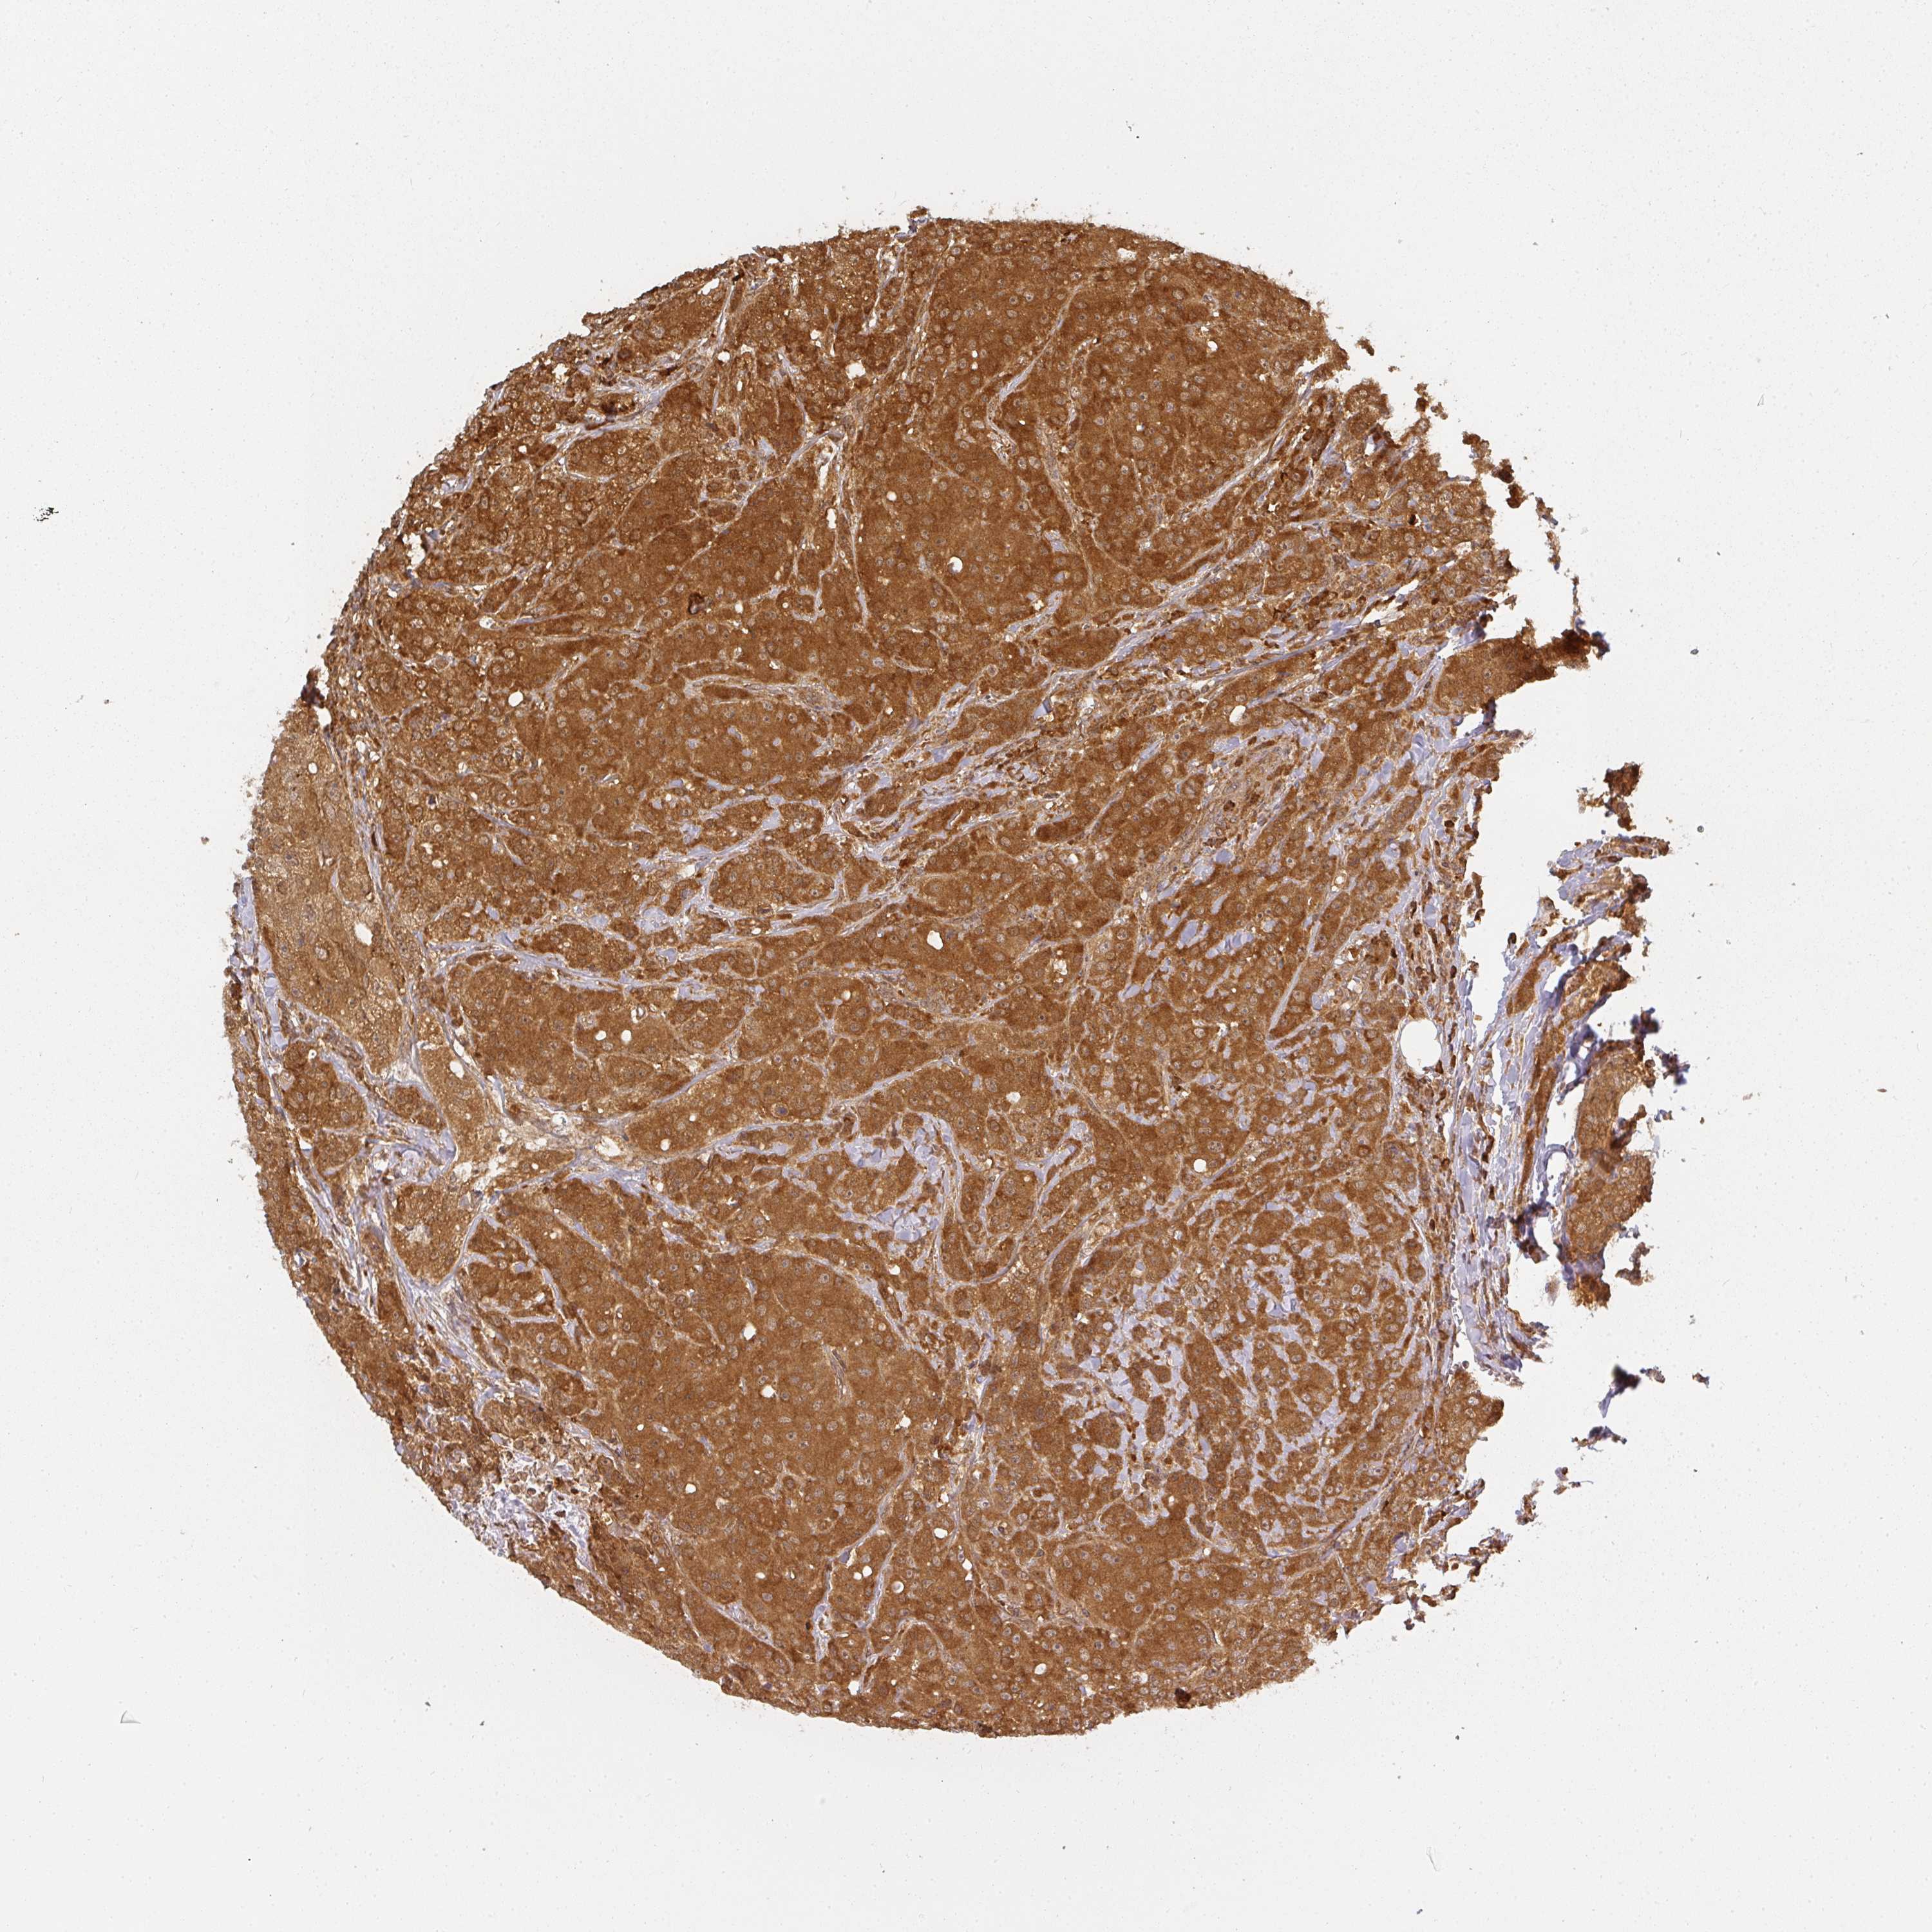

BRCA TCGA BRCA VALIDATION PROTEIN EXPRESSION

ANTIBODIES

AND

VALIDATION